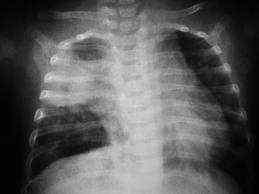

Complicaciones alveolares: atelectasia

La atelectasia es el colapso de los alvéolos (divertículos terminales del árbol bronquial). Puede aparece en zonas localizadas del pulmón o en toda su extensión. Las causas más frecuentes son la obstrucción de las vías aéreas y la ausencia de surfactante en los líquidos que tapizan los alvéolos.

Con respecto a la obstrucción de las vías aéreas, en general sucede que existe un bloqueo de muchos bronquios o de algún bronquio importante por un gran tapón mucoso o por algún objeto sólido, como un tumor. El aire que queda atrapado más allá del bloqueo se absorbe en un plazo de minutos a horas por la sangre que fluye por los capilares pulmonares. Si el tejido pulmonar es lo suficientemente flexible, esto dará lugar simplemente al colapso de los alvéolos. En caso que el tejido pulmonar sea rígido por tejido fibroso y no se pueda colapsar, la absorción del aire desde los alvéolos generará presiones negativas en el interior de los alvéolos, que arrastrará líquido desde los capilares pulmonares hacia estos, haciendo que los alvéolos se llenen completamente con líquido de edema (atelectasia masiva).

El efecto sobre la función pulmonar global que produce la atelectasia masiva de todo un pulmón es, principalmente, el descenso la saturación de oxígeno en sangre. El colapso pulmonar no solo ocluye los alvéolos, sino que casi siempre aumenta la resistencia al flujo sanguíneo a través de los vasos a medida que disminuye el volumen del pulmón. Además, esta hipoxia produce una vasoconstricción adicional.